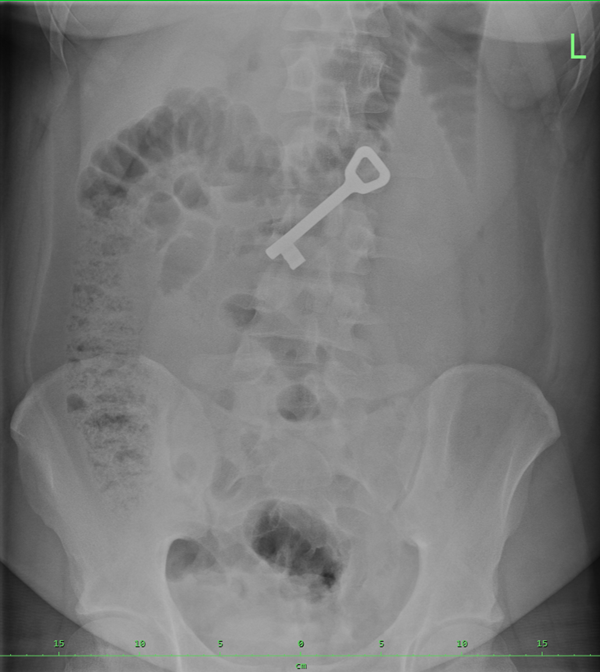

Klíč se nacházel v žaludku mladého pacienta s psychiatrickou diagnózou. Jak kontrastní předmět je výborně viditelný na rentgenu. Bohužel se ukázalo, že v době první gastroskopie je pacient najedený a v žaludku naplněném potravou nešlo klíč nalézt. Klíčem k řešení této situace, abych tak řekl, bylo nechat pacienta několik hodin lačnit, což je nicméně spojené s rizikem, že klíč projde do střev. A skutečně to bylo jen tak tak. Žaludek byl na druhý pokus sice již prázdný, ale klíč v něm nebyl, nalezen byl až pod žaludkem ve vzdálenější části dvanáctníku a jen s obtížemi se ho podařilo zachytit do kličky a vytáhnout k velké radosti nás všech.